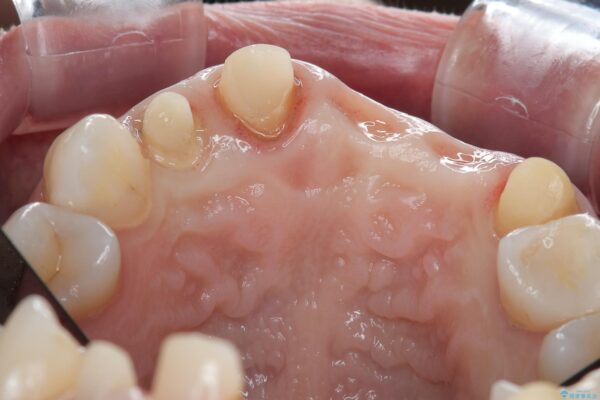

治療計画

一見して問題ないように見える左側の2前歯は、セラミックを除去してみると亀裂や虫歯の再発が見られました。

抜歯時に可及的に歯肉のボリュームを保つよう骨充填材とコラーゲン製剤による填塞を行い審美的かつ機能的なブリッジとなるよう治療を進めます。

治療前

歯槽堤保存術を併用したブリッジ治療 治療前画像 歯槽堤保存術を併用したブリッジ治療 治療前画像 歯槽堤保存術を併用したブリッジ治療 治療前画像 歯槽堤保存術を併用したブリッジ治療 治療前画像 歯槽堤保存術を併用したブリッジ治療 治療前画像 歯槽堤保存術を併用したブリッジ治療 治療前画像 歯槽堤保存術を併用したブリッジ治療 治療前画像 歯槽堤保存術を併用したブリッジ治療 治療前画像 歯槽堤保存術を併用したブリッジ治療 治療前画像 歯槽堤保存術を併用したブリッジ治療 治療前画像